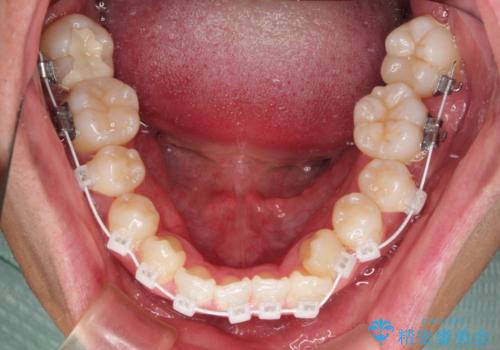

上顎の急速拡大装置を使用して、上顎骨を側方に拡大することで上顎歯列弓を拡大し、それに伴い下顎歯列弓も拡大できるようにして、歯列を整えていくこととしました。

歯列弓の拡大により約1年で矯正治療を終えることができました。

正中も合わせることができ、非常にきれいに仕上がりました。